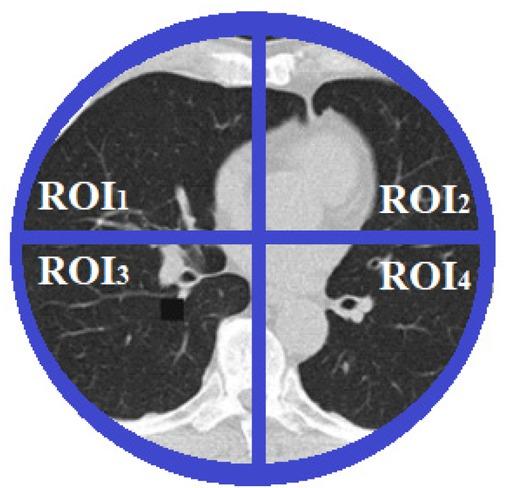

Data used in this paper includes 82 registered signals recorded from 52 patients with lung disorders collected by Dr. Hashemian from the Masih Daneshvari Hospital of Tehran. The sampling frequency is 20 Hz and data are mostely recorded from patients who have had a surgery and were using artificial respiration. For recording the data, a belt with 16 electrodes attached to the device was utilized. This belt have got the ability of adjustment according to the size of an adult’s body and closes below the patient’s breast, right around the lung. The outputs consist of electrical impedance signals of four regions of lungs according to fig. 1. These regions are numbered from 1 to 4. A sample of registrated signals from each region using the EIT system, is depicted in fig. 2. The total of four region’s signals (ROI1 to ROI4) make up the Global signal.

Lungs Classification to four regions.